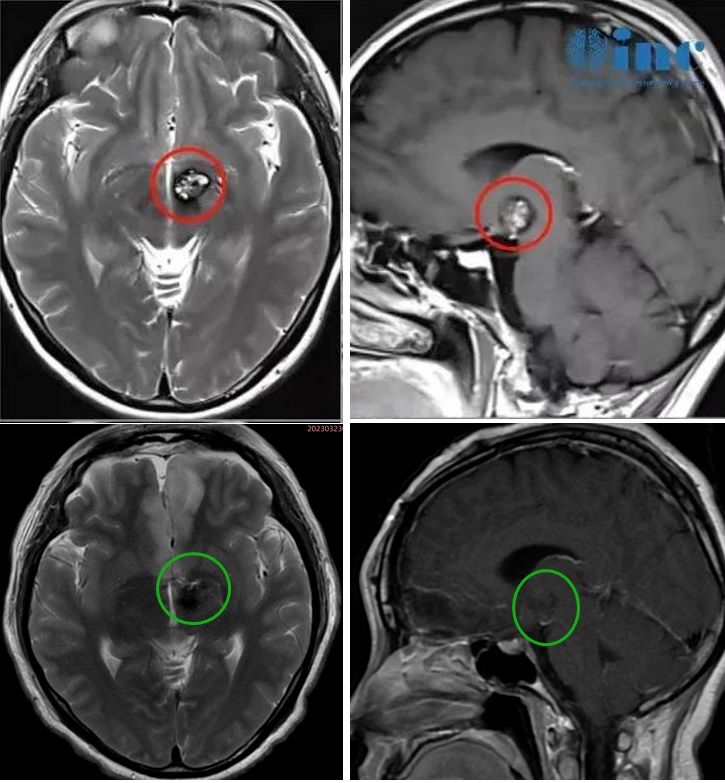

35岁女性-丘脑海绵状血管瘤

患者情况:30岁的文文罹患丘脑基底节海绵状血管瘤,经历多次出血。治疗选择从保守到药物,无法合适缓解症状。症状甚至不断加重,右眼视力下降明显,右下肢无力,步态不稳,复查MRI提示病变增大。但是医生考虑手术并发症和风险过大,还是建议保守治疗。然而多次出血已经无法保守治疗。通过INC远程咨询巴教授之后,得到巴教授可以顺利全切海绵状血管瘤的回复后,文文一家坚定选择这次示范手术。

治疗过程:北京时间3月23日,在苏州大学附属独墅湖医院(苏州独墅湖医院)神经外科手术室,由巴教授主刀,国内神经外科医生辅助配合下,一台丘脑基底节海绵状血管瘤手术顺利完成。这是巴教授2023中国行的一台疑难脑瘤示范手术。

术后情况:术后两周多逐步恢复良好,顺利出院。术后2个月文文恢复良好。

术后4个月:文文行走自如、运动及语言功能良好